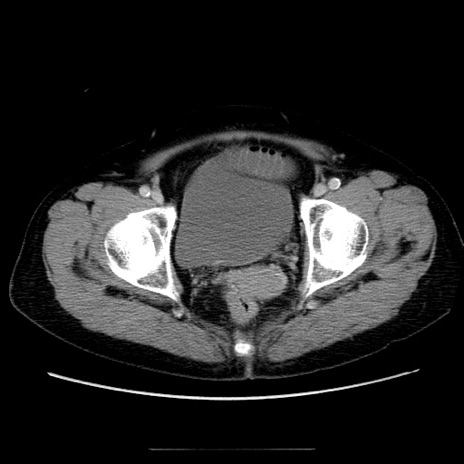

症例5(横断像)

【症例】70歳代女性

【主訴】お腹が張る

【現病歴】1週間くらい前から腹部膨満の自覚あり。昨日夜から増悪したため、本日救急外来受診。

【身体所見】意識清明、BT 36.5℃、BP 165/106mmHg、HR 80bpm、SpO2 98%、腹部:膨満、軟、自発痛・圧痛なし、触診にて不快感あり、腸蠕動音:減弱

【データ】WBC 12600、CRP 1.04